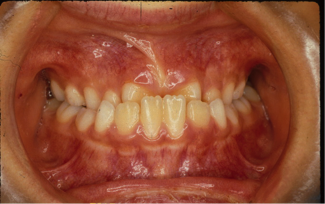

治療前

治療後

前歯で噛む事が出来ないとの悩みから来院された患者様で、開咬症例ではあるのですが突出傾向があったため、小臼歯4本抜歯をする治療方針で約三年ほどかかって治療いたしました。治療後にはきちんとものが噛めるようになり、約三年間の頑張りが報われましたと喜んで頂けました。